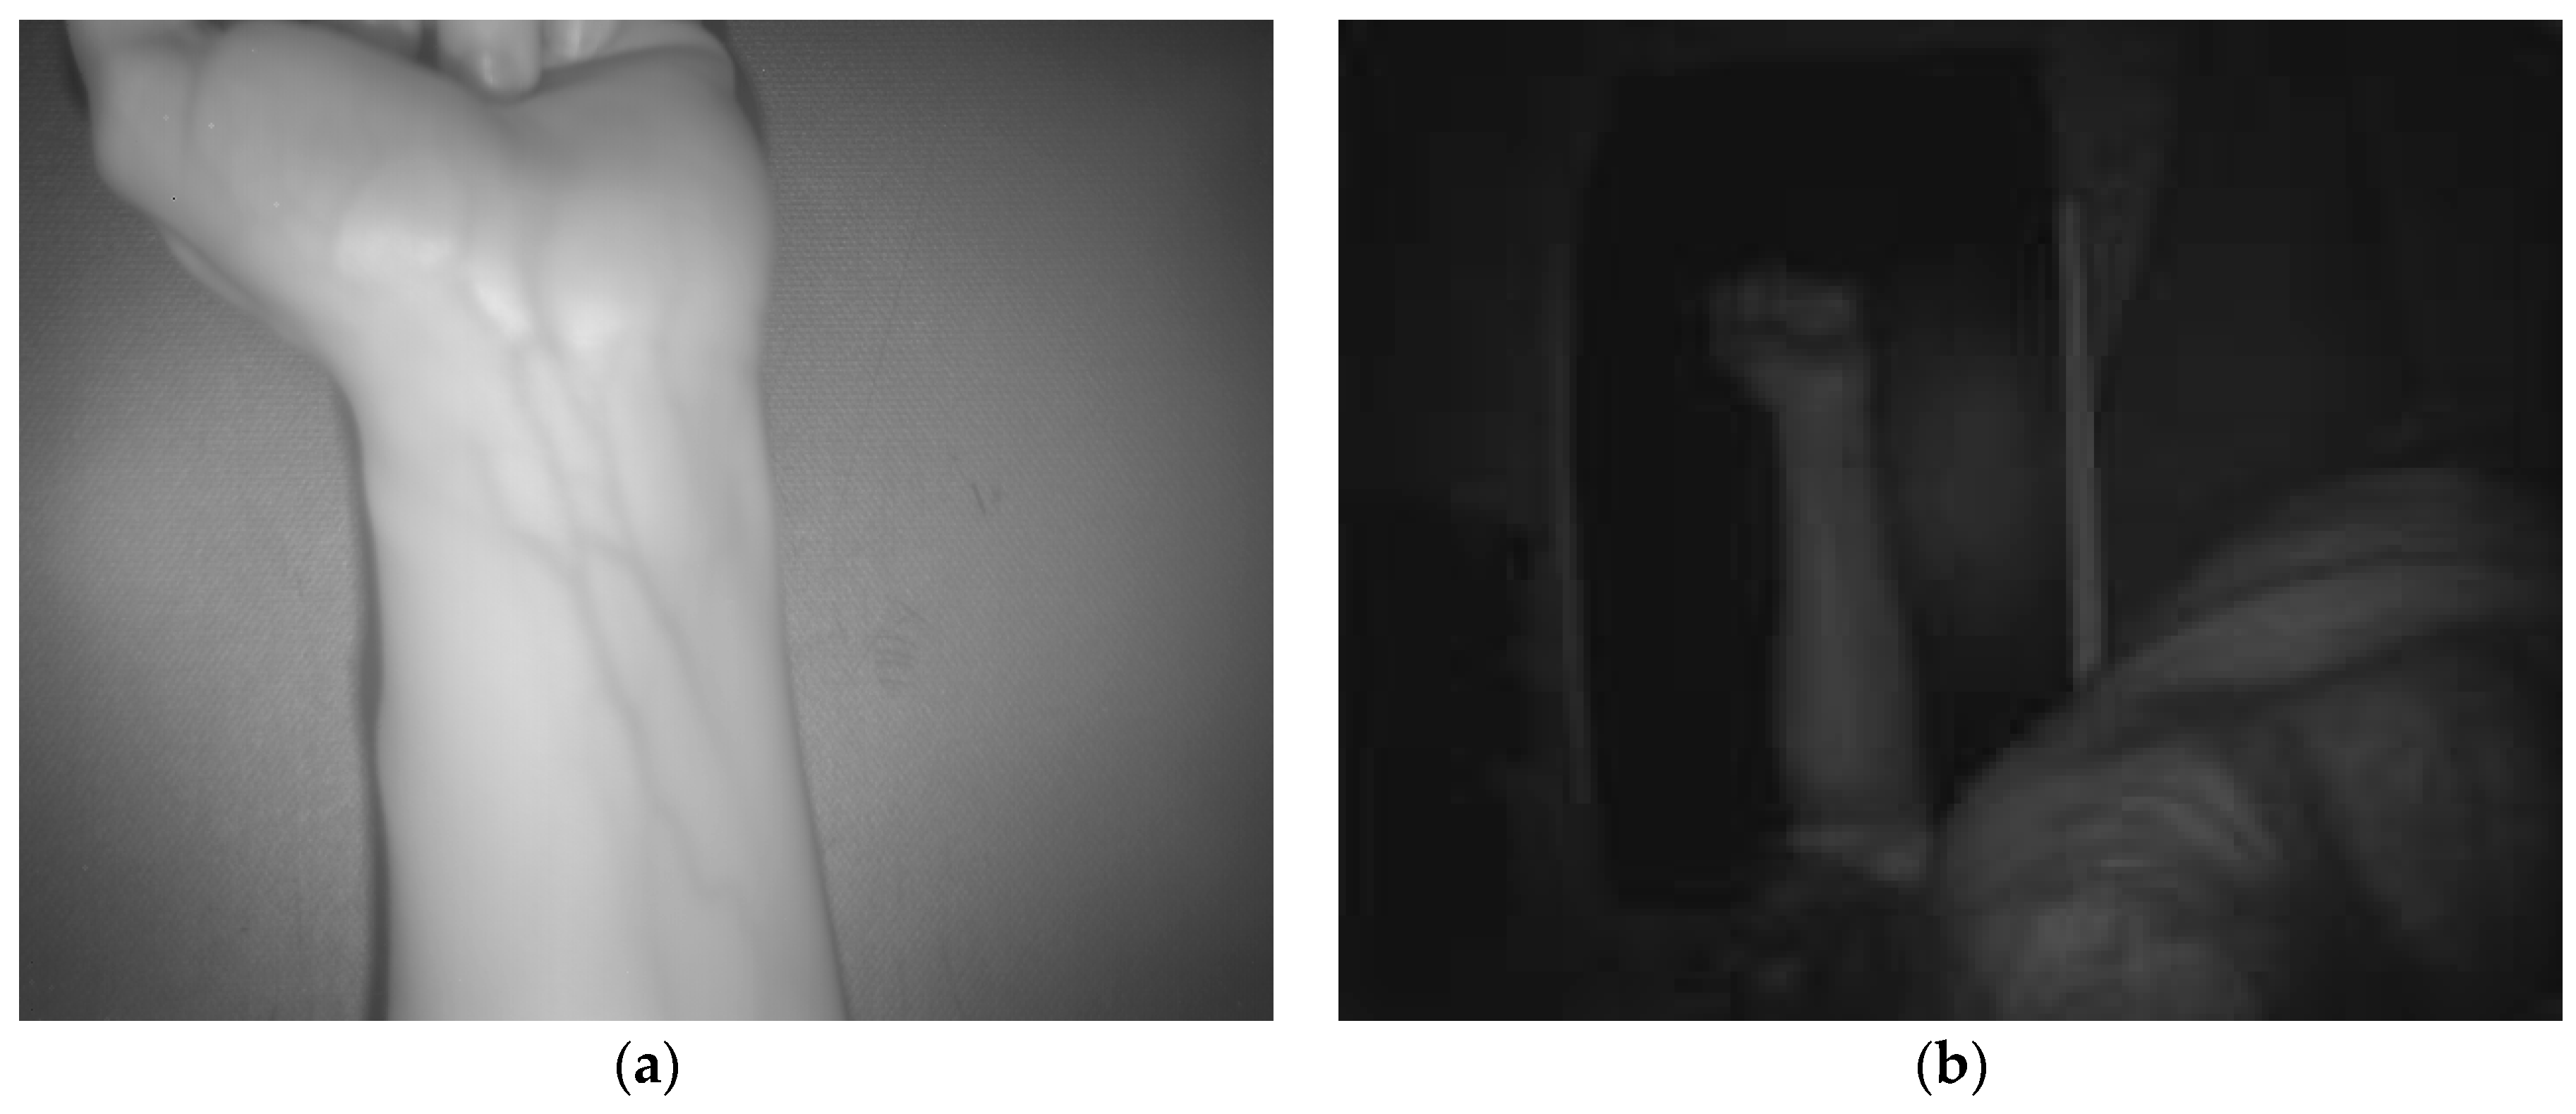

2.1. Multisensory System Description

2.2. Algorithm for Automatic Detection and Localization of Peripheral Subcutaneous Veins